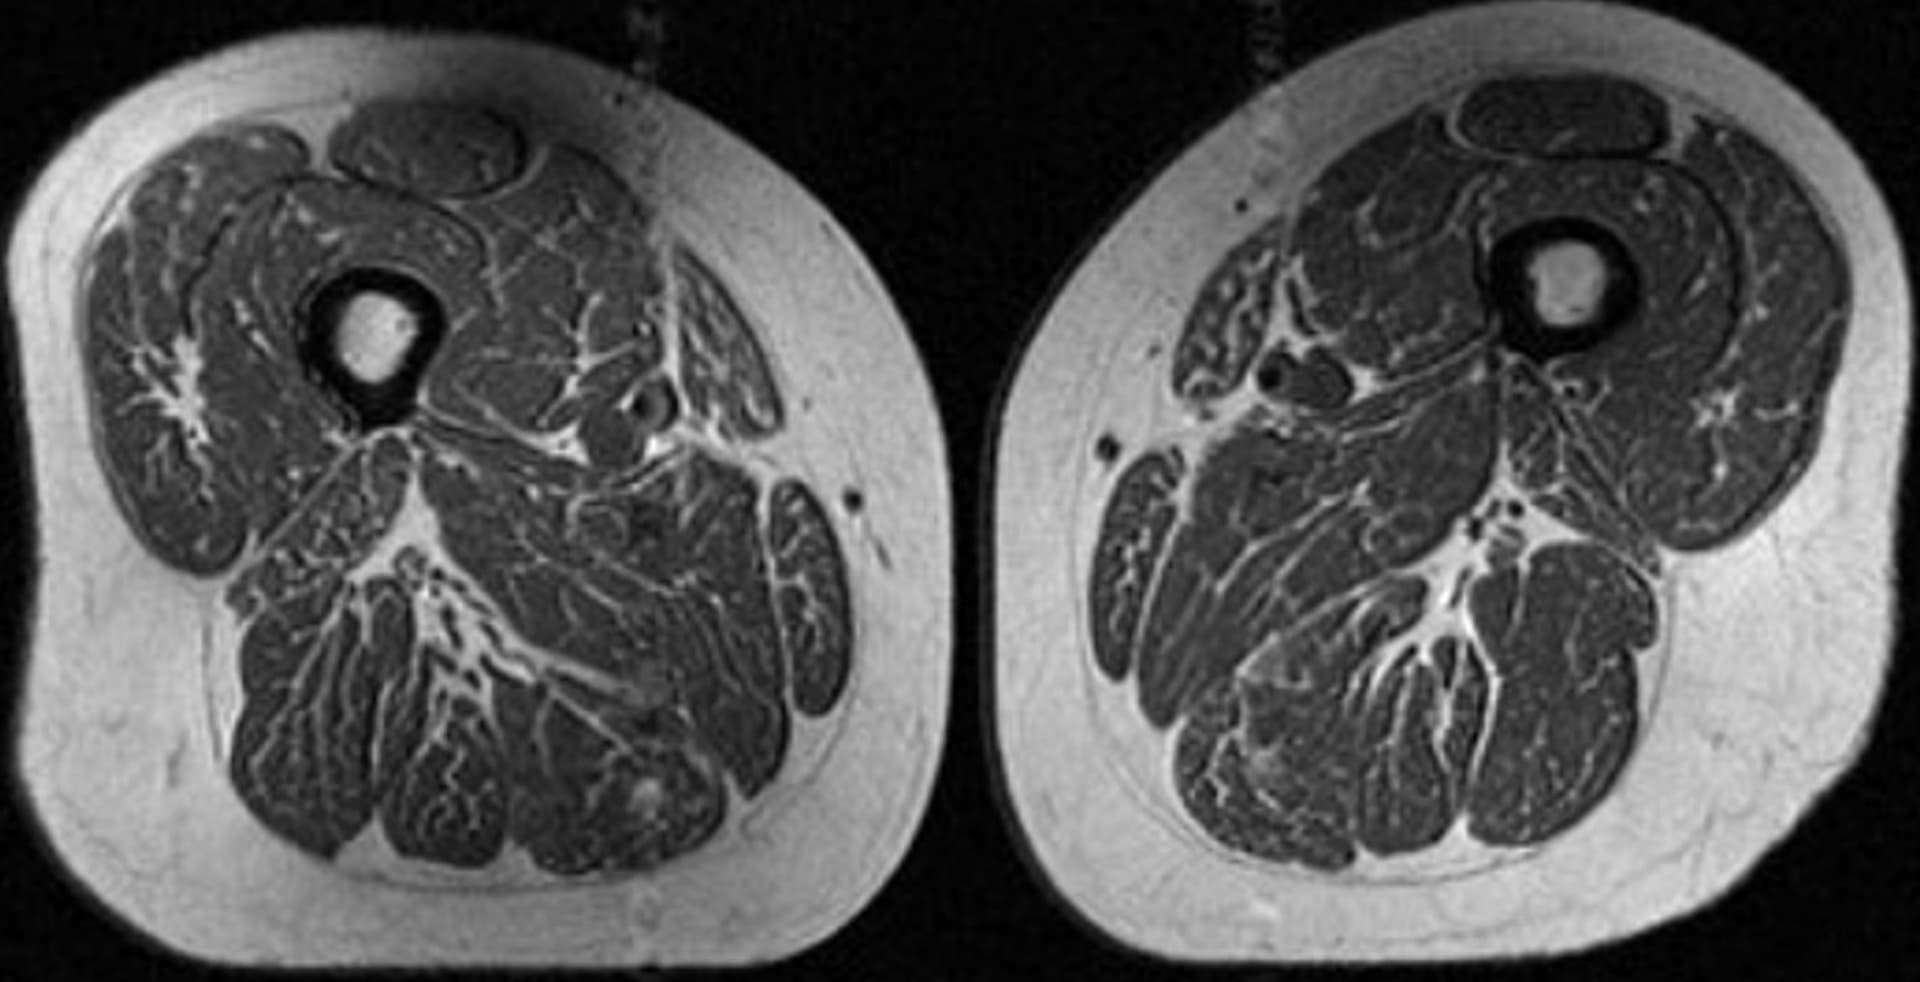

هذه ليس شريحة لحم بل فخذ امرأة.. هكذا تدمر الأطعمة فائقة المعالجة جودة عضلاتك شاهد مقاطع فيديو ذات صلة دبي، الإمارات العربية المتحدة (CNN)-- تبدو هذه الصورة أشبه بشريحة لحم تتمتّع بدرجة عالية من الترخيم (توزيع الدهون)، على نحو قد يذكّرك بقطع اللحم الفاخرة في المطاعم، الغنية بخيوط دقيقة من الدهون المتداخلة.

لكن تُظهر هذه الصورة تصويرًا بالرنين المغناطيسي (MRI) لفخذ امرأة تبلغ من العمر 62 عامًا، كانت تحصل على 87% من سعراتها الحرارية السنوية من الأطعمة فائقة المعالجة.

كما أظهرت امرأة أخرى في الدراسة، تبلغ من العمر 61 عامًا، وجود ترخيم دهني في عضلات فخذها، لكنه كان أقل حدة، إذ شكّلت الأطعمة فائقة المعالجة نحو 29% من نظامها الغذائي السنوي.